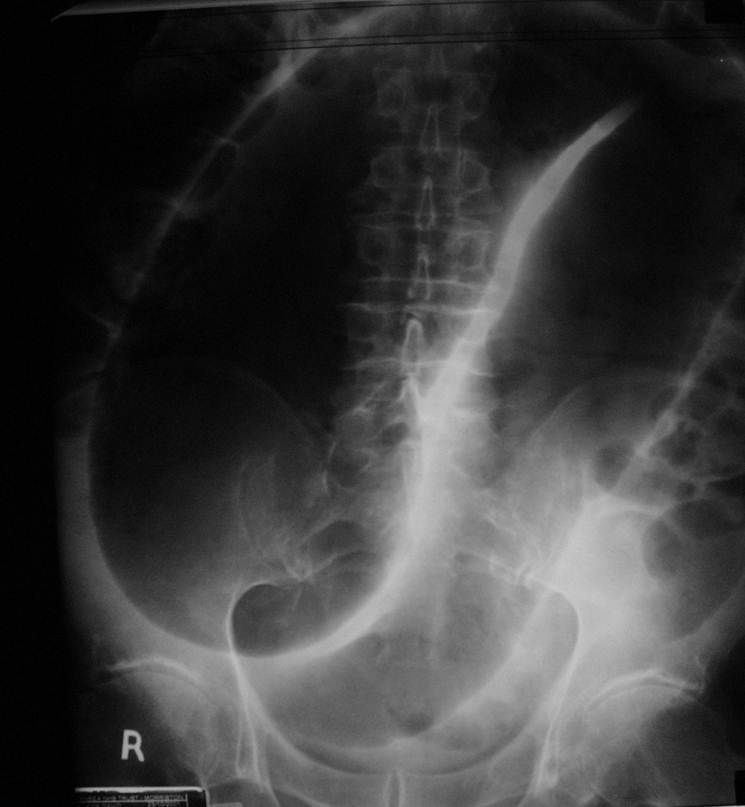

what does this image show?

Dilated Colon - Sigmoid Volvulus

This occurs in cases of long-standing chronic constipation where patients develop a large, elongated, relatively atonic colon, particularly in the sigmoid segment. It is often referred to as acquired or idiopathic megacolon. In sigmoid volvulus, a large sigmoid loop full of faeces and distended with gas twists on its mesenteric pedicle to create a closed-loop obstruction. If uncorrected, venous infarction leads to perforation and faecal peritonitis.